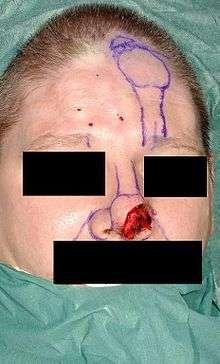

The two most used forehead flap techniques are the two stage and three stage forehead flap.[1][3][4] The forehead consists of multiple layers; skin, subcutaneous tissue, frontalis muscle with fascia and a thin areolar layer.[1][4] Traditionally, the forehead flap is transferred in two stages, where the flap is thinned during the first stage to improve the aesthetic result, possibly jeopardizing its vascularity and increasing chance for flap necrosis. To overcome this problem, Menick[1][3][4] described a three stage forehead flap technique,[1] where initially the flap is transferred containing all tissue layers, making it an extremely safe technique. Only during the second stage, the flap - which now acts as a delayed flap - can safely be thinned aggressively according to aesthetic needs.[1][3][4] During the final stage the pedicle is severed, the flap is thinned further and pedicle and flap are trimmed and inset. This three stage flap is especially useful for reconstructing large defects, complex contour deformations, or lining defects, while the two stage flap is used for smaller and superficial defects.[1][4]

Before surgery all important landmarks and reference points must be identified and marked. Important landmarks are the hairline, frown lines, location of the supratrochlear vessels, ouline of the defect, nasal and lip subunits.[1] Then templates are made using the intact side of the nose to make a precise symmetric reconstruction of the nose. The template resembling the defect is placed just under the hairline and the vascular pedicle is drawn downwards into the medial eyebrow. The pedicle is based on the supratrochlear vessels and can be 1.2 cm wide.[1] This way the flap design has been made.

First stage

The flap is incised and elevated from distal to proximal.[1][3] Distally, the frontalis muscle and subcutaneous tissue are excised, this is done for 1.5 to 2 cm.[1][3] Then more downwards the disscection goes through the muscle and over the periosteum.[1] When reaching the brow, all of the skin borders are incised and the flap is carefully released.[1] As soon as the flap reaches the defect without tension further incision of the flap is stopped and the flap is inset into the area of the defect.[1][3][4] This is done using a single layer of fine suture.[1]

First stage

The flap is incised and elevated over the periosteum from distal to proximal.[1] The flap consists of skin, subcutaneous tissue, fat and frontalis muscle and is not thinned. When reaching the brow, all of the skin borders are incised and the flap is carefully released.[1] The full-thickness flap is then sutured into the defect without tension.